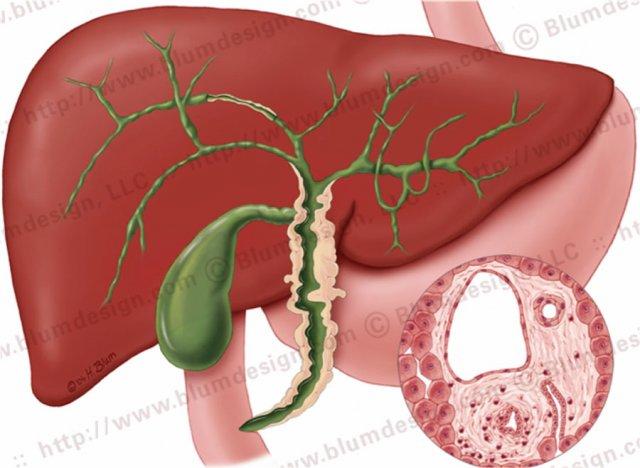

Viêm xơ đường mật nguyên phát với các chỗ hẹp ở cả đường mật trong gan và ngoài gan. Minh họa bởi Heike Blum

Đặc điểm điển hình của PSC là các chỗ hẹp, tuy nhiên ở giai đoạn sớm của bệnh, các chỗ hẹp này có thể khó nhận biết.

Bất thường nền tảng trong PSC là xơ hóa, với căn nguyên chưa được xác định.

PSC có mối liên quan chặt chẽ với viêm loét đại tràng ở tới 70% bệnh nhân, nhưng cũng có thể liên quan đến bệnh Crohn của đại tràng.

Lý do của mối liên quan với bệnh viêm ruột (IBD) vẫn chưa được biết rõ, nhưng được cho là kết quả của một phản ứng miễn dịch.